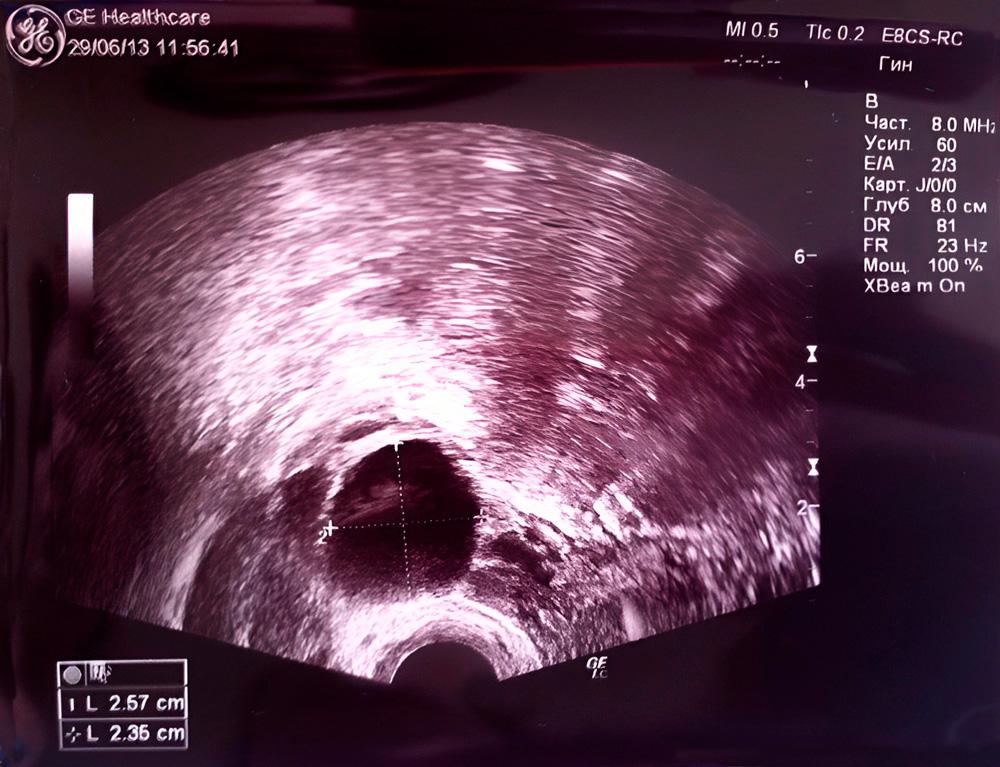

La primera imagen fue tomada a la mitad del ciclo menstrual, el contorno oscuro del útero es claramente visible en la misma. Las áreas claras en la cavidad uterina son la membrana mucosa o endometrio. En la segunda fase del ciclo, la progesterona suaviza el endometrio para que un óvulo fertilizado pueda adherirse fácilmente a las paredes del útero.